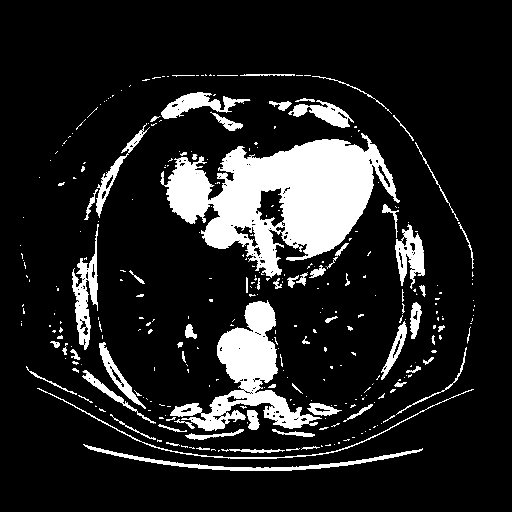

Original NATIVE CT scan (input)

Full window (WL 1023.5, WW 4095 β†’ Low βˆ’1024, High +3071)

Actual HU range: [-1024.0, 3071.0]